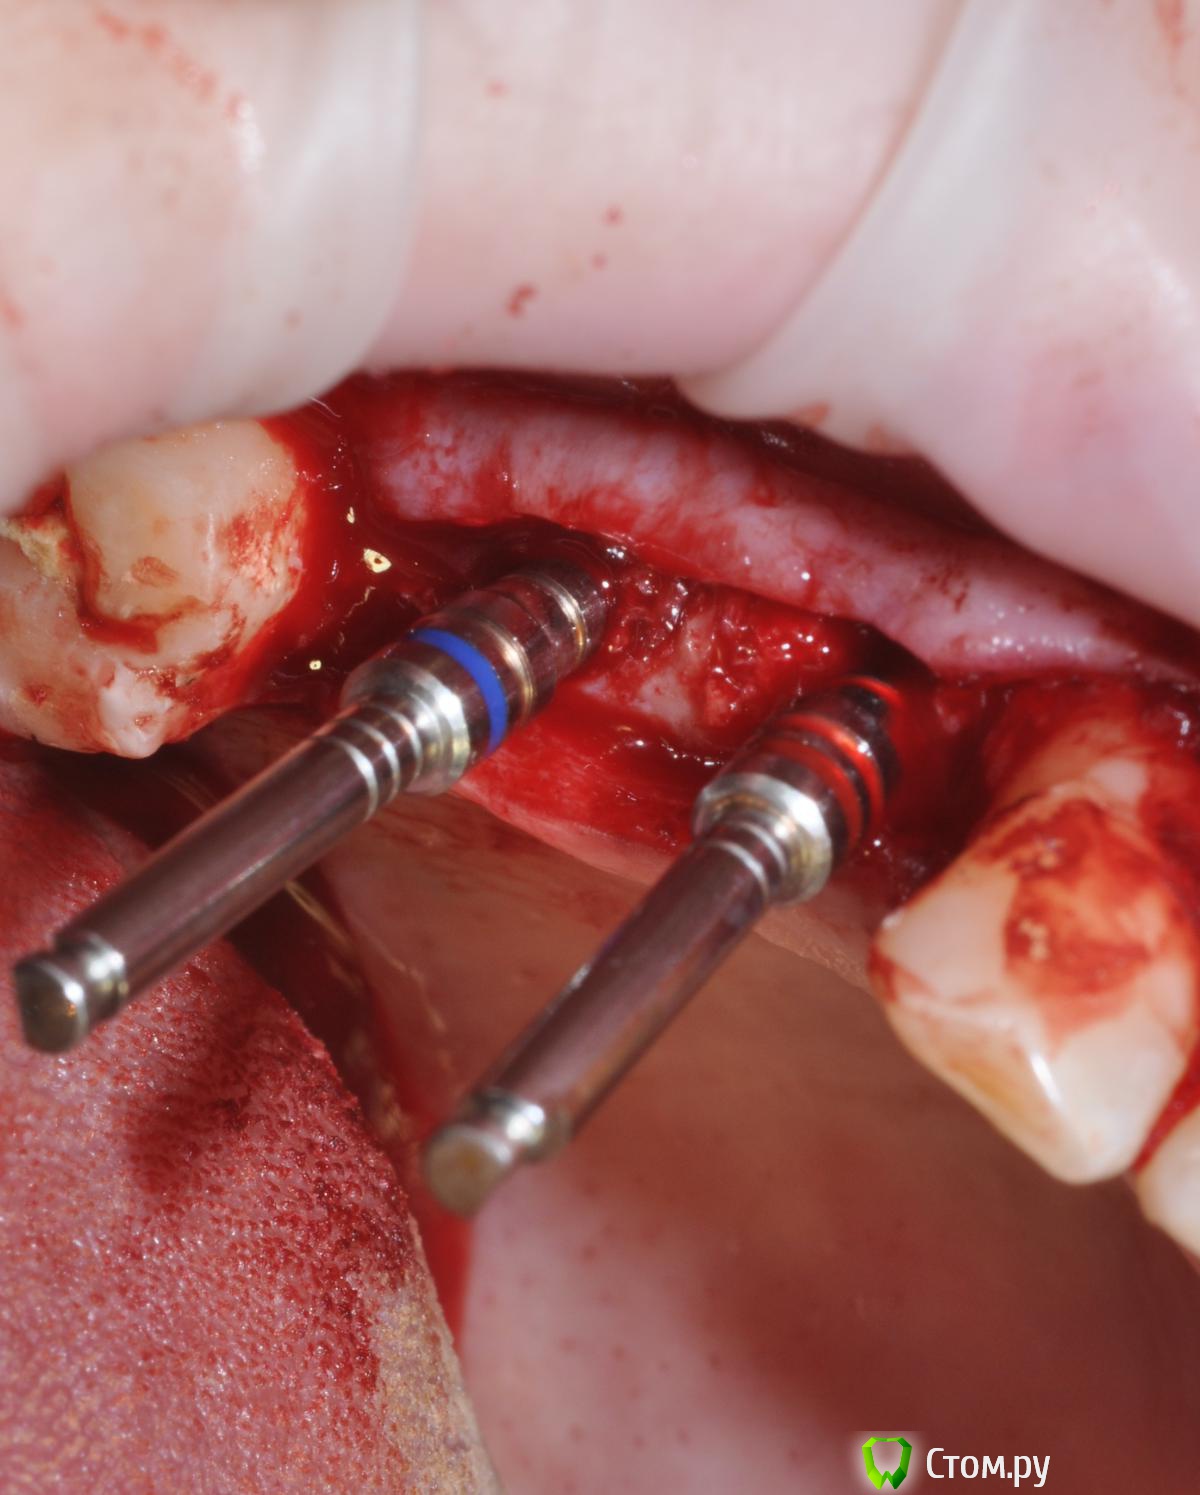

StomDoc Опубликовано 4 марта, 2014 Поделиться Опубликовано 4 марта, 2014 (изменено) Просьба высказать свое мнение о сложившейся ситуации. Была установка имплантата и НКР с мембраной и пинами с вестибулярной стороныБ 3 месяца никаких жалоб, на установке формирователя все вытекло, даже крошки никакой не было. Возможно что хромает техника. Фотографий именно этой имплантации нет, но есть похожая было сделано все так же но пока не открывал еще, Изменено 4 марта, 2014 пользователем StomDoc Ссылка на комментарий

StomDoc Опубликовано 6 марта, 2014 Автор Поделиться Опубликовано 6 марта, 2014 (изменено) Спасибо по поводу слизистой так и сделано прикрыл сст!!!! имплантат устанавливался вровень с язычной стенкой присыпалось только с вестибулярной стороны!!! Надо поискать кт до импл!!!кости изначально наваломнужно было имплант глубже и язычнее наклонить и никаких пластик ( имхо)далее удалить 48 и дистализировать 47в данной ситуации просто пересадить сст жирный язычно и вестибулярноЕсли наклонять язычно то протезировать проблематично же будет вроде!!)))У ортопедов в гос поликлинике другой план, депульпировать 47 и вывести вкладкой)))) Изменено 6 марта, 2014 пользователем StomDoc Ссылка на комментарий

doca Опубликовано 6 марта, 2014 Поделиться Опубликовано 6 марта, 2014 С чего бы ей расплываться????Сорри,не увидел фото с пинами ,она была с самого начала?.Кстати, почему-то уверен,что в кейсе на верхней челюсти все будет ок.А вот внизу непонятно,возможно все-таки с фиксацией были проблемы или с недостатком питания графта или дефект все же другой был .А зачем вы так сильно раскрылись вокруг импланта? Ссылка на комментарий

StomDoc Опубликовано 6 марта, 2014 Автор Поделиться Опубликовано 6 марта, 2014 Сорри,не увидел фото с пинами ,она была с самого начала?.Кстати, почему-то уверен,что в кейсе на верхней челюсти все будет ок.А вот внизу непонятно,возможно все-таки с фиксацией были проблемы или с недостатком питания графта или дефект все же другой был .А зачем вы так сильно раскрылись вокруг импланта?При первом разрезе сразу вытекла желтая жидкость вот и решил проверить что там с графтом!!! Мембраны всегда фиксирую пинами и прошиваю с язычной стороны!!!! Ссылка на комментарий

doca Опубликовано 6 марта, 2014 Поделиться Опубликовано 6 марта, 2014 При первом разрезе сразу вытекла желтая жидкость вот и решил проверить что там с графтом!!! Мембраны всегда фиксирую пинами и прошиваю с язычной стороны!!!!значит, просто ,инфекция. 1 Ссылка на комментарий

StomDoc Опубликовано 6 марта, 2014 Автор Поделиться Опубликовано 6 марта, 2014 значит, просто ,инфекция. Спасибо я тоже к этому склоняюсь!!!мне главное что не техника виновата!! Завтра кт выложу может и правда сдесь без графта можно было!!! Ссылка на комментарий